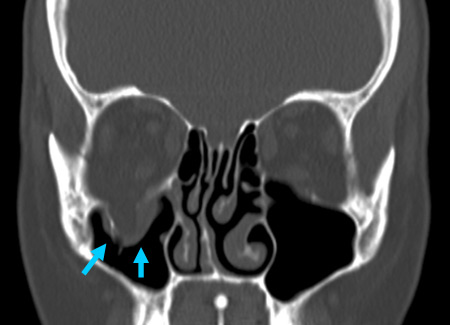

Fine-cut spiral CT with coronal and sagittal reconstructions. [Figure caption and citation for the preceding image starts]: Right orbital blow-out fracture on CT-scan; coronal reformatFrom the personal collection of Dr Alistair Cobb [Citation ends].

[Figure caption and citation for the preceding image starts]: Right orbital blow-out fracture on CT-scan; sagittal reformatFrom the personal collection of Dr Alistair Cobb [Citation ends].

[Figure caption and citation for the preceding image starts]: No evidence of fracture on the left orbit as seen on CT-scan; sagittal reconstructionFrom the personal collection of Dr Alistair Cobb [Citation ends].